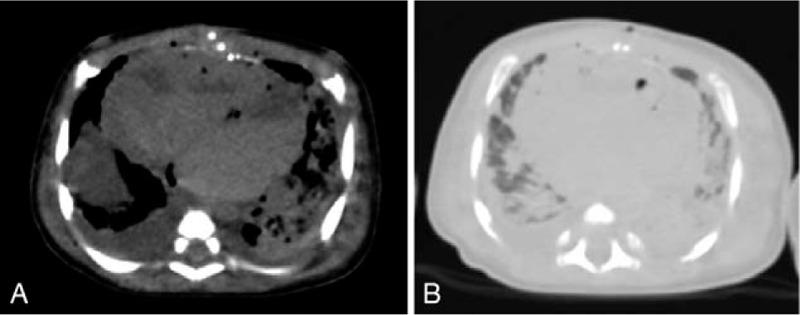

日本一家三级护理医院中,非增强型尸检计算机断层扫描在3岁及以下儿童院内非创伤性死亡调查中的应用

Utility of unenhanced postmortem computed tomography for investigation of in-hospital nontraumatic death in children up to 3 years of age at a single Japanese tertiary care hospital.

To evaluate the utility of unenhanced postmortem computed tomography (PMCT) for the investigation of in-hospital nontraumatic death in children up to 3 years of age.This study included the cadavers of children who died from intrinsic diseases before 3 years of age. The major underlying disease and the main organ-disease systems associated with the immediate causes of death were determined by clinical evaluation, PMCT, and autopsy, which were used as a reference standard. The rates of concordance between the former two methods and autopsy were calculated for all cases.In total, 22 cadavers (12 male and 10 female; mean age, 6.1 ± 8.2 months) were included. The rates of concordance between clinical evaluation/PMCT and autopsy for diagnosis of the major underlying disease and main organ-disease systems associated with the immediate causes of death were 100%/36% (P = .0015) and 59%/41% (P = .37), respectively. In cases where the respiratory system was associated with the immediate cause of death, PMCT showed greater diagnostic sensitivity (90%) than did clinical evaluation (20%). In contrast, the diagnostic sensitivity of PMCT was lower than that of clinical evaluation in cases involving disorders of the cardiac system and multiple organ systems (0% vs 100% for both).The findings of this study suggest that the use of unenhanced PMCT with clinical evaluation can result in improved detection of the immediate cause of death in select cases of in-hospital nontraumatic death before 3 years of age.

摘要

评估非增强型尸检计算机断层扫描(PMCT)在调查3岁以下儿童院内非创伤性死亡中的应用价值。本研究纳入了3岁前因内在疾病死亡的儿童尸体。通过临床评估、PMCT和作为参考标准的尸检来确定主要潜在疾病以及与直接死因相关的主要器官疾病系统。计算前两种方法与尸检在所有病例中的一致性率。总共纳入了22具尸体(12例男性和10例女性;平均年龄6.1±8.2个月)。临床评估/PMCT与尸检在诊断主要潜在疾病以及与直接死因相关的主要器官疾病系统方面的一致性率分别为100%/36%(P = 0.0015)和59%/41%(P = 0.37)。在呼吸系统与直接死因相关的病例中,PMCT显示出比临床评估更高的诊断敏感性(90%对20%)。相比之下,在涉及心脏系统和多器官系统疾病的病例中,PMCT的诊断敏感性低于临床评估(两者均为0%对100%)。本研究结果表明,在3岁以下儿童院内非创伤性死亡的特定病例中,结合临床评估使用非增强型PMCT可提高对直接死因的检测。